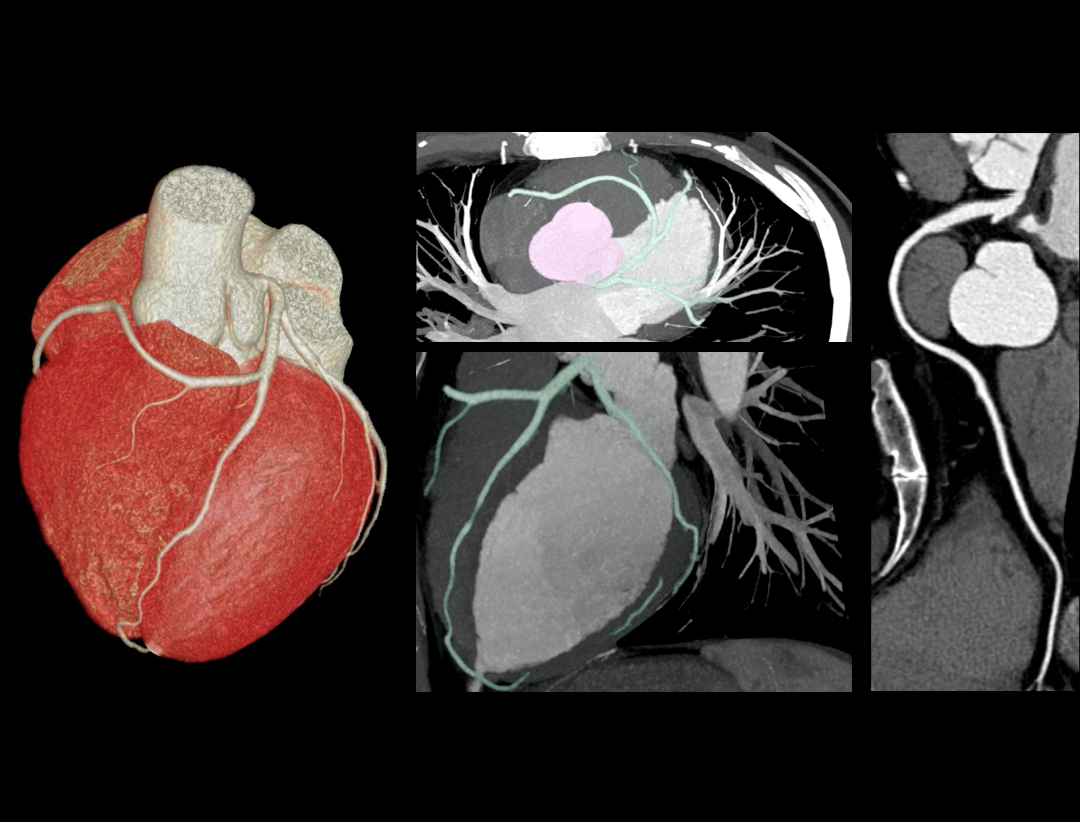

Excellence in Cardiac Imaging

CardioXphase

最適位相の自動選択。

100kW Max Generator Power

解剖学的構造を明瞭に描出。

0.3s Rotation Speed

時間分解能の向上。

Adaptive And Intuitive Applications

ワンクリック操作でより簡便な後処理の実現。

High Heart Rate: 101 bpm

Mixed Coronary Atherosclerotic Plaque

Anomalous Origin Of Coronary Artery